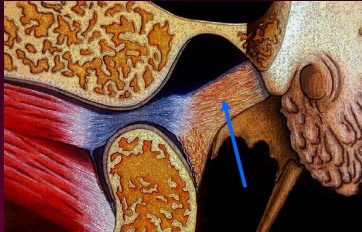

Q

A

Retrodiscal Connective Tissue (a.k.a. bilaminar zone)